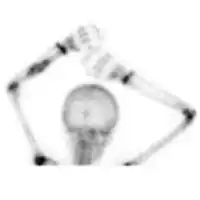

| Diagnostic method | Medical imaging. CT scan and X-ray: lytic expansion lesion its clear border. MRI: fluid levels. Bone scan: peripheral radiotracer uptake, with a central Photopenic area.[1] |

X-ray and CT scan show lytic expansion lesions with clear borders.[1] Expansion of cortex gives the lesion a balloon-like appearance. Larger lesions may appear septated.[10] MRI reveals fluid levels.[1] Bone scan shows outer radiotracer uptake, with a central dark area.[1]

Bone scan: ABC left radius